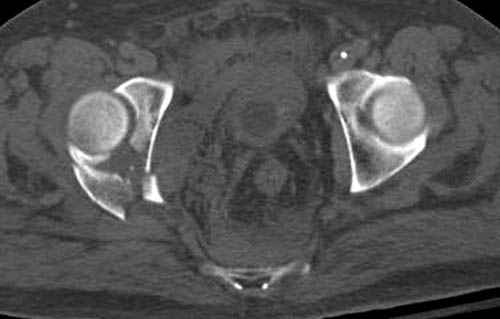

По возможности вышлите снимки, сканы таза до

реконструкции, интраоперационные.

По снимку создается впечатление о высоком поперечном переломе, задней колонны, стенки; почему не пользовались *magic screw*?

Снимки здесь....